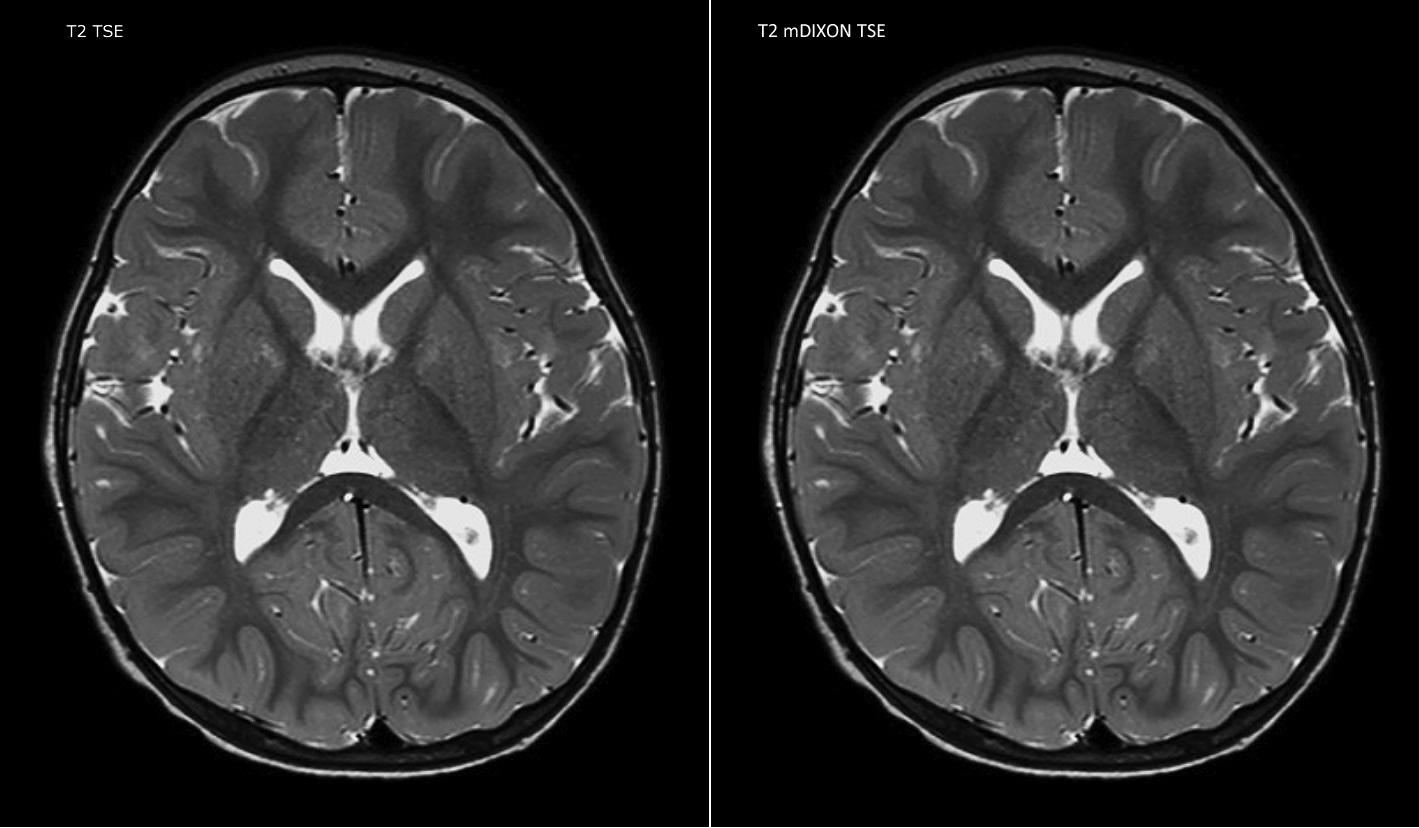

Philips mDIXON TSE is a two-point DIXON technique that separates water and fat signals, for time-efficient fat-free imaging, even in challenging neuro anatomy. “mDIXON TSE has been one of the most significant improvements in imaging sequences that we have utilized to date at PCH,” says Dr. Miller. “Its multi-parametric acquisition allows us to obtain fat suppressed images and equivalent non-fat suppressed T2 images all in the same sequence. In addition, prior methods of fat suppression could be artifactually corrupted by poor patient anatomy or poor operator application, but with mDIXON we now have a robust and reliable method of fat suppression.” Fat saturation is historically challenging at the ends of fields of view, especially in total spine imaging and in difficult patient anatomy such as the lower regions of the neck. “Due to the unique fat suppression capabilities of mDIXON, however, these challenges no long apply,” says Dr. Miller. “We routinely obtain homogeneous fat suppression under virtually all conditions. It has also led to some efficiencies by not having to repeat sequences because of that technical failure.”

“mDIXON TSE has increased our diagnostic confidence in ruling in or ruling out abnormalities in which fat suppression is critical to diagnosis, such as metastatic disease or osseous abnormalities.”

“mDIXON TSE is most useful in patients with lesions or abnormalities in the soft tissues such as the face and neck, and for patients with contrast enhancing abnormalities that are mostly visible with fat suppression,” says Dr. Miller. “All our spine imaging now routinely contains mDIXON water-only T2 images, and this allows us to identify pathology that may be obscured by non-fat suppressed imaging such as injuries of the bone. And it’s not necessary to obtain additional standard TSE T2 images because the in-phase mDIXON images are equivalent to standard TSE T2 images.”